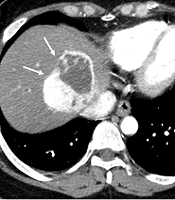

Therapeutic Effects of CT-guided Microwave Ablation Combined with Cementoplasty in the Treatment of Bone Metastasis

Bin Hao,

Jian Ma,

Ningjun Wan,

Shaowei Xu,

Zhen Wang*